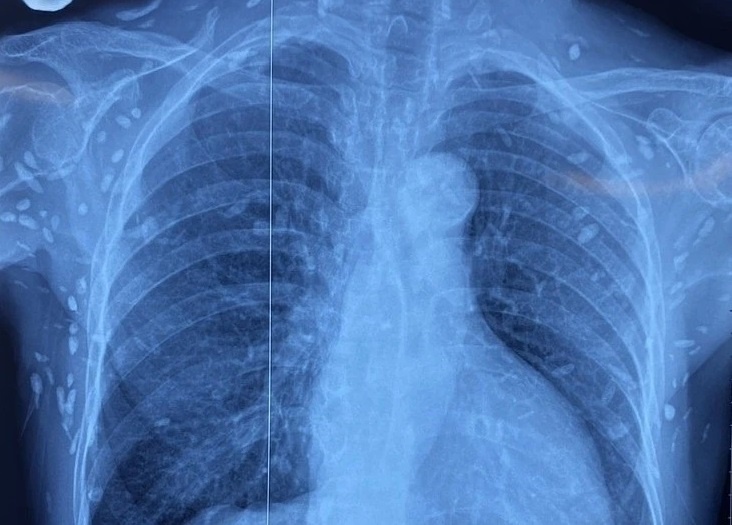

Hình ảnh sán xuất hiện khắp cơ thể người bệnh. Ảnh: Bệnh viện Trung ương Quân đội 108. |